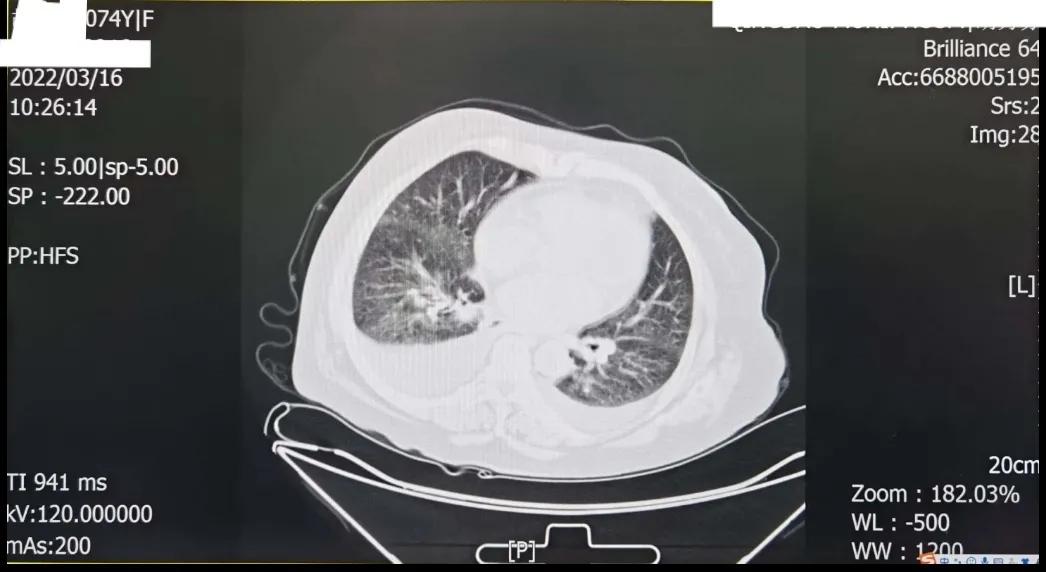

很快,患者就携带检查结果回到了诊室。心电图显示窦性心律、大致正常,心率也无明显增快;心脏彩超提示左房扩大(43.2mm)、二尖瓣退变并返流(中量)、三尖瓣返流(少量),但左室不大、EF正常(64%);BNP仅轻微增高(199.2pg/mⅠ)(正常范围0~100pg/mⅠ),且不说我们平素诊治的那些心衰患者BNP动辄要升高若干倍,若该患者确有心衰,这BNP结果也与患者如此严重的双下肢水肿根本不符;胸部CT虽然显示双侧少量胸腔积液,但无明显肺瘀血征象,显然,患者不能诊断为“心衰”,双下肢水肿也就不能用心衰来解释。

胸部CT平扫显示肺纹理粗乱、透亮度减低,可见双侧胸腔积液,主动脉、冠状动脉钙化